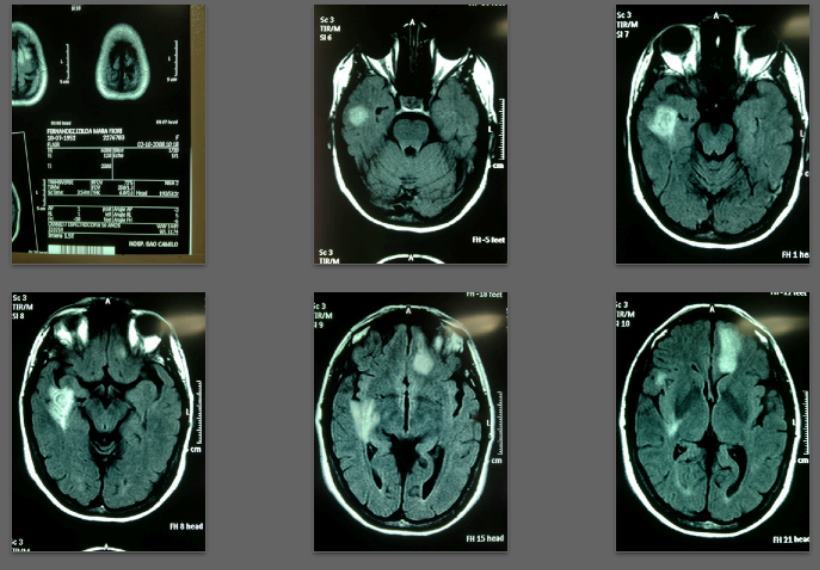

Before/after MRI images for one of 1,000+ patients of Dr. Coimbra

2008 Convulsive seizures Diagnosis: Balo’s concentric hemiparesis

Starting daily dose 25,000 IU; increased in stages to 80,000 IU on October 28, 2010. Asymptomatic since 2010.

2008 MRI